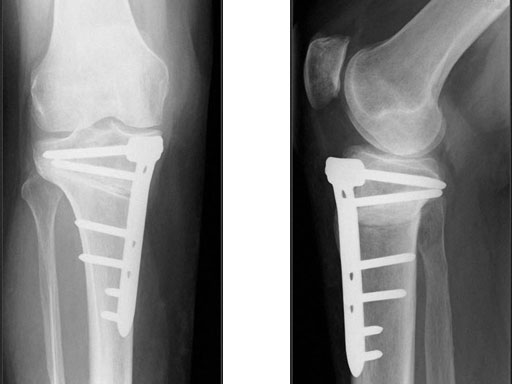

A 68-year-old female.

Case provided by Alex Staubli, Luzern, CH

The correction is planned on a long-leg standing x-ray. After surgery, the mechanical axis should pass through a point 63% on the lateral side of the total width of the tibial plateau in the frontal plane. A transverse or slightly oblique incision is used to avoid damage to the saphenous nerve. The distal fibers of the medial collateral ligament are detached from the tibia. Under fluoroscopic control, two wires are placed in the proximal tibia marking the transverse osteotomy plane. The cut usually starts at the upper margin of the pes anserinus and ends at the tip of the fibula on the lateral side. The wires are placed exactly parallel to the tibial plateau thus taking into consideration the individual tibial slope of the patient. An incomplete cut of the posterior two-thirds of the proximal tibia is performed with an oscillating saw guided by the wires. Continuous irrigation avoids burn injury to the bone. A second osteotomy is now performed in the anterior third of the tibia in an angle of 100 ending above the patellar tendon insertion. A smaller saw blade is used and the complete anterior cortex is cut exactly in the frontal plane. The osteotomy is now gradually opened by inserting flat chisels or a spreader-chisel into the posterior osteotomy cleft. This process may take some minutes and can usually be completed without fracture of the lateral cortex. A bone spreader is now placed in the posteromedial edge of the tibia and the chisels are removed. The leg is extended and the correction is checked with the fluoroscope. A long metal rod is placed between center of the hip joint and center of the ankle joint. The projection of this rod should be at the planned point of correction on the tibial plateau lateral of the midline. Eccentric collapse of the medial joint space may cause accidental overcorrection. In this case pressure on the foot may simulate loading and body weight. The correction can be fine-tuned by opening or closing the spreader. The TomoFix Medial Tibia Plate is now placed in a subcutaneous pocket. The implant is precontoured and usually fits well to the bone surface. The distance holders avoid compression of the medial collateral ligament and the pes anserinus. Three proximal bolts are placed near the subchondral sclerosis zone. The position of the bolts is adapted to the anatomy of the proximal tibia giving optimum purchase for the bolts. An oblique lag screw is inserted distal to the osteotomy. This screw in the first combination hole allows careful compression of the lateral osteotomy hinge and pretensioning of the implant. A stab incision is created on the shaft and the implant is fixed monocortically with bolts. The lag screw and the distance holders are replaced by bolts. The medial collateral ligament is released longitudinally to reduce medial compartment pressure and the wound is closed in layers. An overflow drain may be used. Clinical and experimental work has proven that when this technique is closely followed, corrections up to and over 15 mm can be performed without bone grafting or use of bone substitutes.

The patient is mobilized on crutches on day one after surgery. Partial weight bearing is allowed from the beginning. Biomechanical and RSA studies have proven that postoperative loading of the implant by body weight in standard partial weight bearing and early full weightbearing conditions did not cause loss of correction. Our group now allows the patients to walk without crutches as soon as the postoperative pain allows after this type of surgery. Members of the Knee Expert Group (KNEG) have presently implanted over 1,500 TomoFix medial tibia. The results are extremely positive in respect to osteotomy healing, implant failure, and surgical complications.